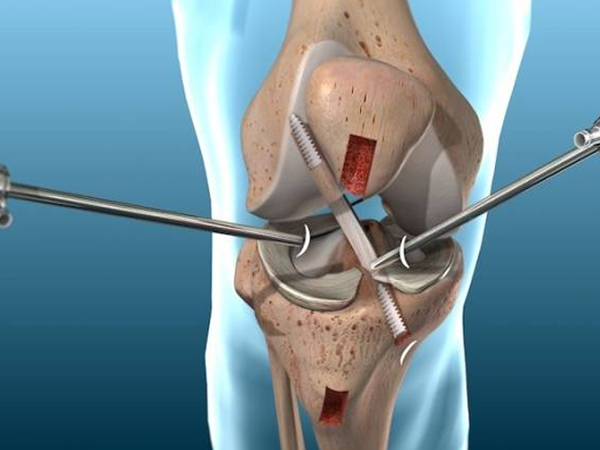

Robotic & Conventional Joint Replacement